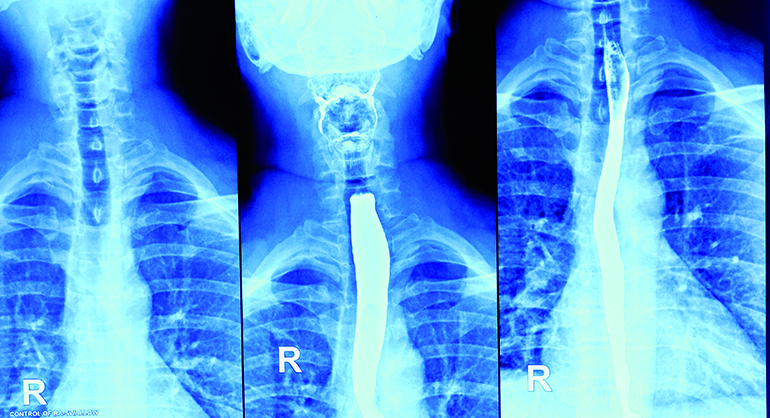

La deglución es un acto tan cotidiano que su enorme complejidad pasa inadvertida hasta que deja de funcionar como debería. Detrás de este gesto automático se esconde una precisa coordinación neuromuscular entre la boca, la faringe, la laringe y el esófago. Cuando este mecanismo falla aparece la disfagia, un trastorno que dificulta el paso seguro de alimentos, líquidos o incluso saliva.